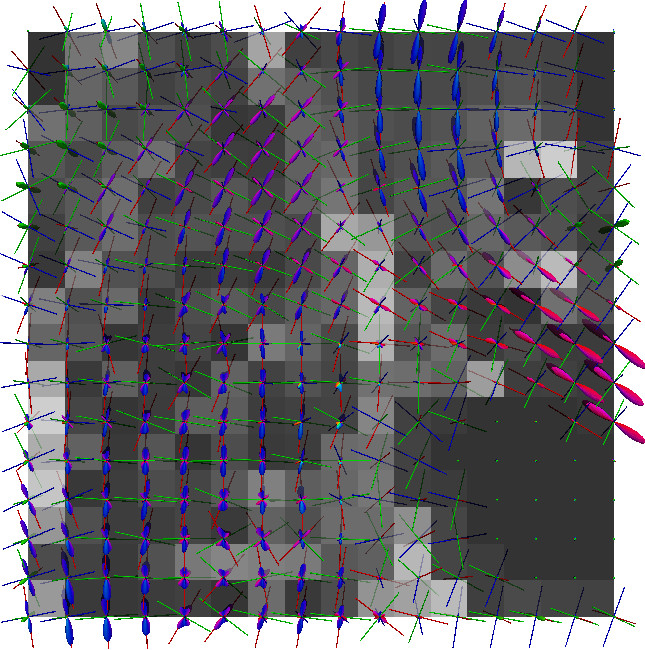

Non-negative spherical deconvolution (NNSD) (Cheng et al., 2014) is performed to estimate non-negative fiber ODFs from three-shell DWI data. NNSD works for multi-shell data. It is more robust to noise, and the obtained fiber ODFs (fODFs) in isotropic regions are closer to the isotropic spherical PDF, compared with conventional constrained spherical deconvolution (Tournier et al., 2007). After obtaining the fODFs by NNSD, the peaks are detected from the estimated fODFs with GFA larger than , as described in Section 3.4. OO and OD are calculated from the spherical harmonic representation of fODFs along their principal peaks as shown in Algorithm 1. The second row in Fig. 11 demonstrates FA from tensors estimated by DTI, OO and OD from fODFs estimated by NNSD, and the total distortion map estimated from the local orthogonal frames of fODFs. Fig. 12 and 13 show the close-up views of fODFs, local orthogonal frames, and the six proposed indices for the red and blue regions in Fig. 11, where the region shown in 12 is also visualized in the DFA pipeline in Fig. 1. The fODF glyphs are colored by using its sampled directions. The three orientations in the local orthogonal frame in each voxel are visualized by using three tubes in red, green, and blue colors respectively. There is no local orthogonal frame in some voxels because those voxels have GFA values lower than . These figures show the following: 1) OO is high in anisotropic areas with well-aligned directions, while OD is high in isotropic or crossing areas. 2) The four orientational distortion indices are low in areas with well aligned principal directions, and zero in isotropic voxels without peaks. Distortion indices are high in voxels where the principal directions in its local neighborhood change largely. 3) The central voxels in red region is the crossing area of the Corpus Callosum from left to right and Fornix that goes through the coronal slice. The twist index showed high value in this crossing area as expected.

We perform whole brain streamline tractography on the estimated fODF field using mrtrix (Tournier et al., 2012) 888http://www.mrtrix.org/. The voxels with GFA larger than are used as seed voxels to generate tracts by using tckgen in mrtrix. All other parameters are default parameters in mrtrix. The obtained fiber tracts are then visualized by using trackvis 999http://trackvis.org. Fig. 14 and 15 demonstrate the tracts respectively cross two given ball ROIs. The tracts are colored by using the proposed six scalar indices. Note that the proposed scalar indices are calculated based on estimated fODFs, not based on fiber tracts. It can be seen that 1) OO is high in areas with well aligned fibers, while OD is high in crossing areas and distortion areas; 2) distortion indices are low when fibers are well aligned; 3) the total distortion index is high in areas with highly curved fibers or crossing fibers. 4) although splay, bend, twist indices may be separable (e.g., one is large while another one is close to zero) in synthetic data, in real data, these three types of distortions normally occur together, especially for bending and splaying. 5) the ROI in Fig. 14 is the crossing area of the Corpus Callosum and the Fornix, where all distortion indices have high values, especially for twist and total distortion indices. This finding agrees with Fig. 12.